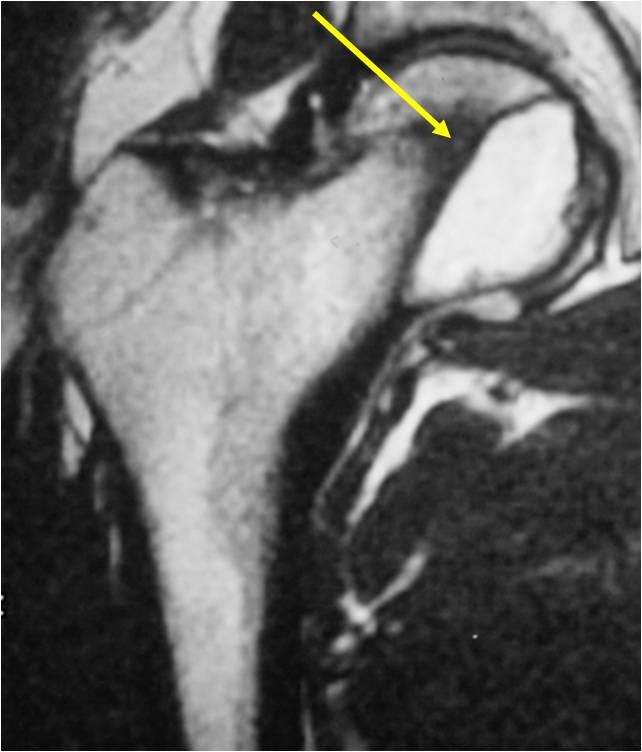

Radiographic Presentation

- Usually osteolytic, expansile lesion

- May be focally calcified

- Often a sharp interface between tumor and surrounding bone

- Sclerotic rim is uncommon

- Overlying cortex is usually thin, but intact